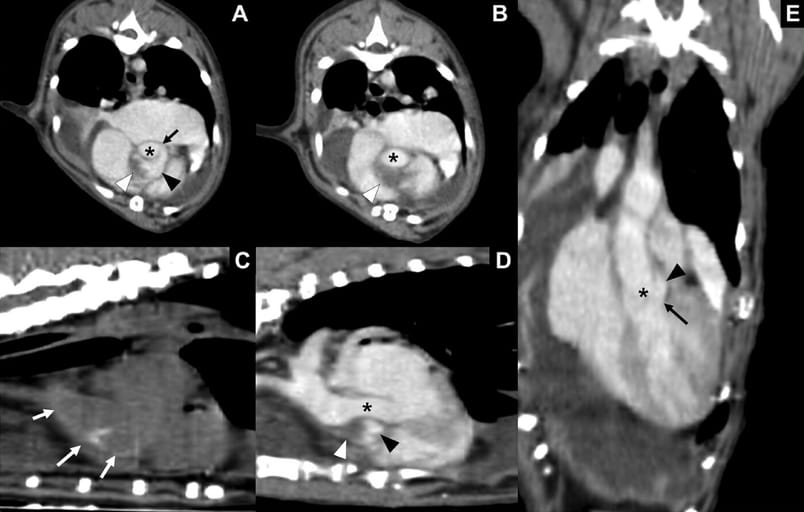

Axial (A, B) and multi-plane reconstructed CT images (C-E) of the aortic dissection. The true lumen (black asterisk) and false lumen (black arrowhead) of the aorta connected through a defect suspected as a dissection (black arrow) was identified (A). The false lumen of the aorta (black arrowhead) and non-contrast enhanced lesion (white arrowhead) composing a beak-shaped lesion (B), which compresses the true lumen of the aorta from the axial and reconstructed images are shown (A, B, D, E). A pre-contrast reconstructed image shows aortic wall calcification (white arrow) from the aortic root to the ascending aorta (C). Note that the calcification is most prominent at the level of dissection. Panel D shows dissection compressing the true lumen of the aorta at the level of the aortic root. The connection between the true lumen and false lumen (asterisk) through a defect (black arrow) (E) on the dorsal image is shown. Marked pleural effusion is observed throughout the CT images. CT, computed tomography.

Initial echocardiography showed a false lumen compressing the true aortic lumen, with jet flow indicating communication between the two. CT confirmed a 2.7 mm wall defect at the aortic valve with a spiral, beak-shaped false lumen compressing the ascending aorta. The cat developed pericardial effusion, chylothorax, and renal impairment over the follow-up period. Post-mortem examination confirmed a full-thickness dissection and a false lumen larger than the true lumen. Histology revealed dissection at the tunica media, myocardial hypertrophy, and fibrosis consistent with HCM phenotype.